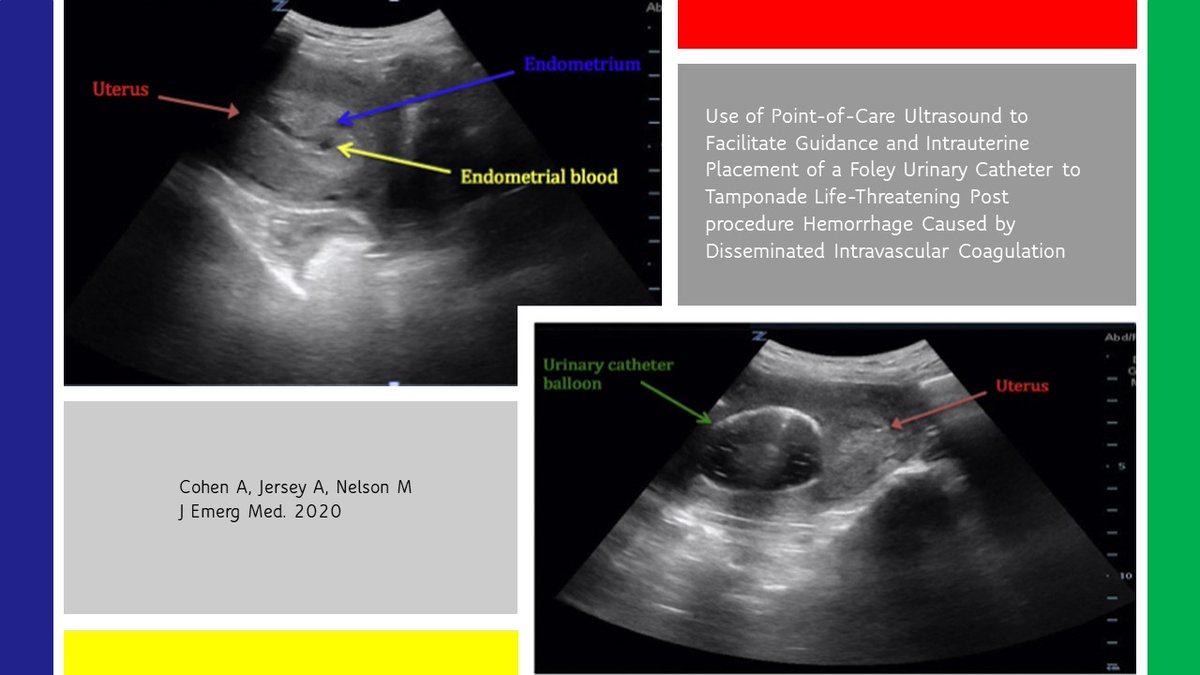

#POCUS guided placement of an intrauterine urinary catheter in the setting of disseminated intravascular coagulation. Interesting case report: https://www.ncbi.nlm.nih.gov/pubmed/31982201#emergencymedicine pic.twitter.com/DIlGimKa1w